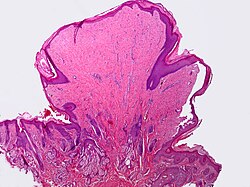

| Keratoacanthoma | keratin plug, glassy pink cytoplasm, pushing downward growth | minimal/no nuclear atypia | grow rapidly then involute | none | squamous cell carcinoma | some don't believe in the entity | |